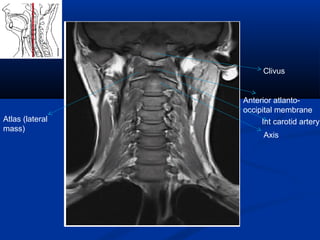

Clivus

Anterior atlanto-

occipital membrane

Atlas (lateral

mass)

Axis

Int carotid artery